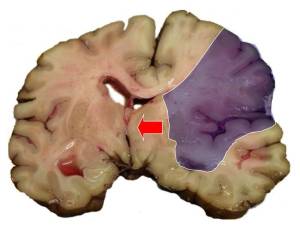

Sağlamlıq Sağlamlıq İnsult – beyin qan dövranının kəskin pozulması nəticəsində baş beyində ocaqlı zədələnmənin yaranması ilə xarakterizə olunur. İşemik və ya hemorragik x Laura's 1 28.10.2024

Sağlamlıq Sağlamlıq İnsult – beyin qan dövranının kəskin pozulması nəticəsində baş beyində ocaqlı zədələnmənin yaranması ilə xarakterizə olunur. İşemik və ya hemorragik x Laura's 162 28.10.2024